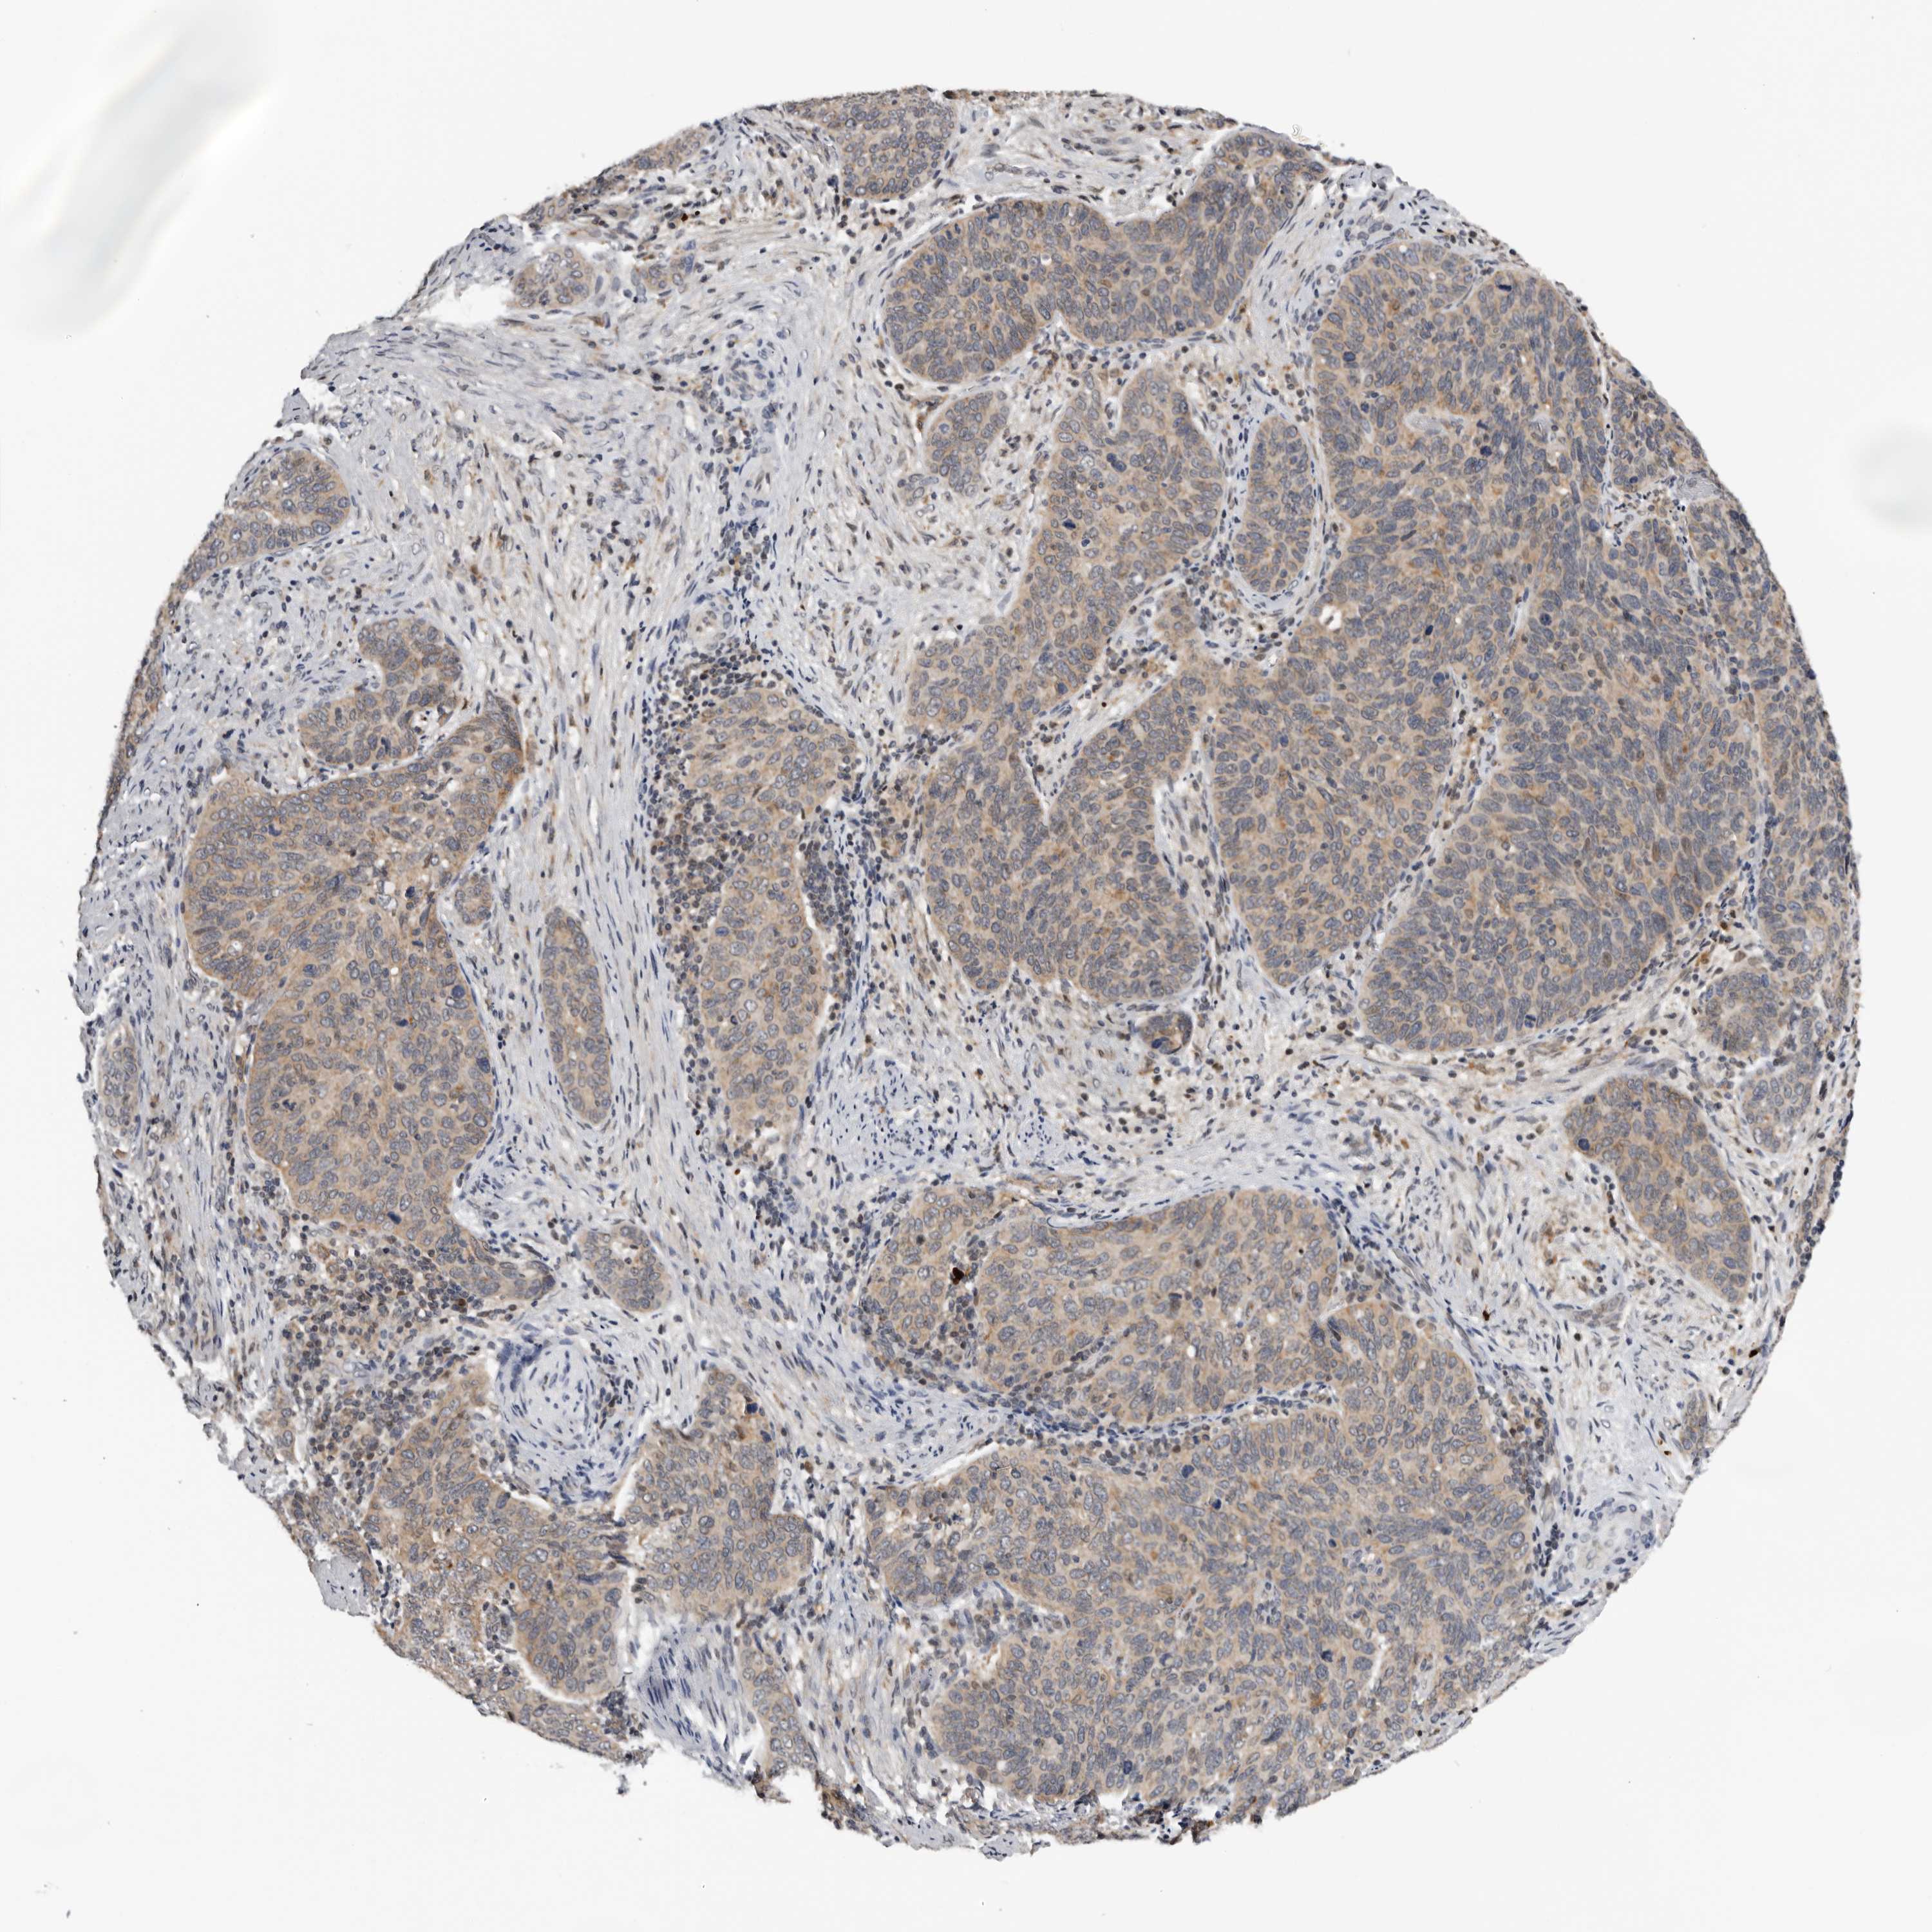

CERVICAL CANCER - Protein expressioni

A mouse-over function shows sample information and annotation data. Click on an image to view it in a full screen mode. Samples can be filtered based on level of antibody staining by selecting one or several of the following categories: high, medium, low and not detected. The assay and annotation is described here.

Note that samples used for immunohistochemistry by the Human Protein Atlas do not correspond to samples in the TCGA dataset.

Antibody stainingi

Antibody staining in the annotated cell types in the current human tissue is reported as not detected, low, medium, or high, based on conventional immunohistochemistry profiling in selected tissues. This score is based on the combination of the staining intensity and fraction of stained cells.

Each image is clickable and will lead to virtual microscopy that enables deeper exploration of all samples and also displays staining intensity scores, fraction scores and subcellular localization as well as patient and tissue information for each sample.

Antibody HPA023081

Antibody HPA023103

Antibody HPA024795

Squamous cell carcinoma, NOS

Adenocarcinoma, NOS